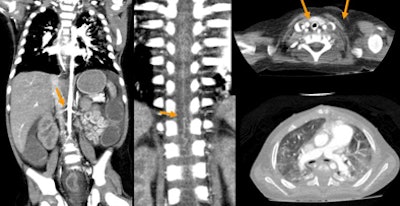

| Patient with stridor and giant cervical hemangioma was breathing continuously and not sedated during 320-detector-row CT, acquired in two rotations at 0.35 sec, 80 kV, 20 mA, and dose of 0.3 mSv. Below, additional rotation allows reconstruction of images at multiple time points, revealing air trapping that would have been missed at single-rotation scan. |